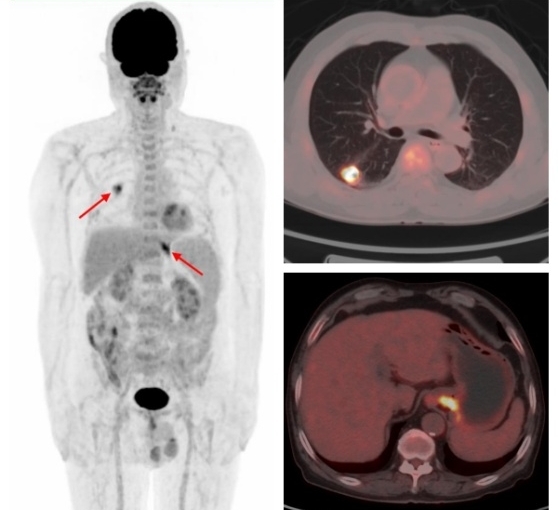

三、檢測第二原發(fā)性惡性腫瘤

國際頂級腫瘤期刊《美國醫(yī)學(xué)會雜志腫瘤學(xué)(JAMA Oncology)》的數(shù)據(jù)顯示,65歲以上的老年癌癥患者二次患癌的概率為25.2% 。多原發(fā)癌好發(fā)于消化系統(tǒng)、呼吸系統(tǒng)和泌尿系統(tǒng)。有研究發(fā)現(xiàn)FDG PET/CT在3%的非小細(xì)胞肺癌患者中發(fā)現(xiàn)了第二原發(fā)性惡性腫瘤或癌前病變,從而改變了27%的患者的治療方案。

原發(fā)肺腺癌合并賁門腺癌

原發(fā)肺鱗癌合并直腸腺癌